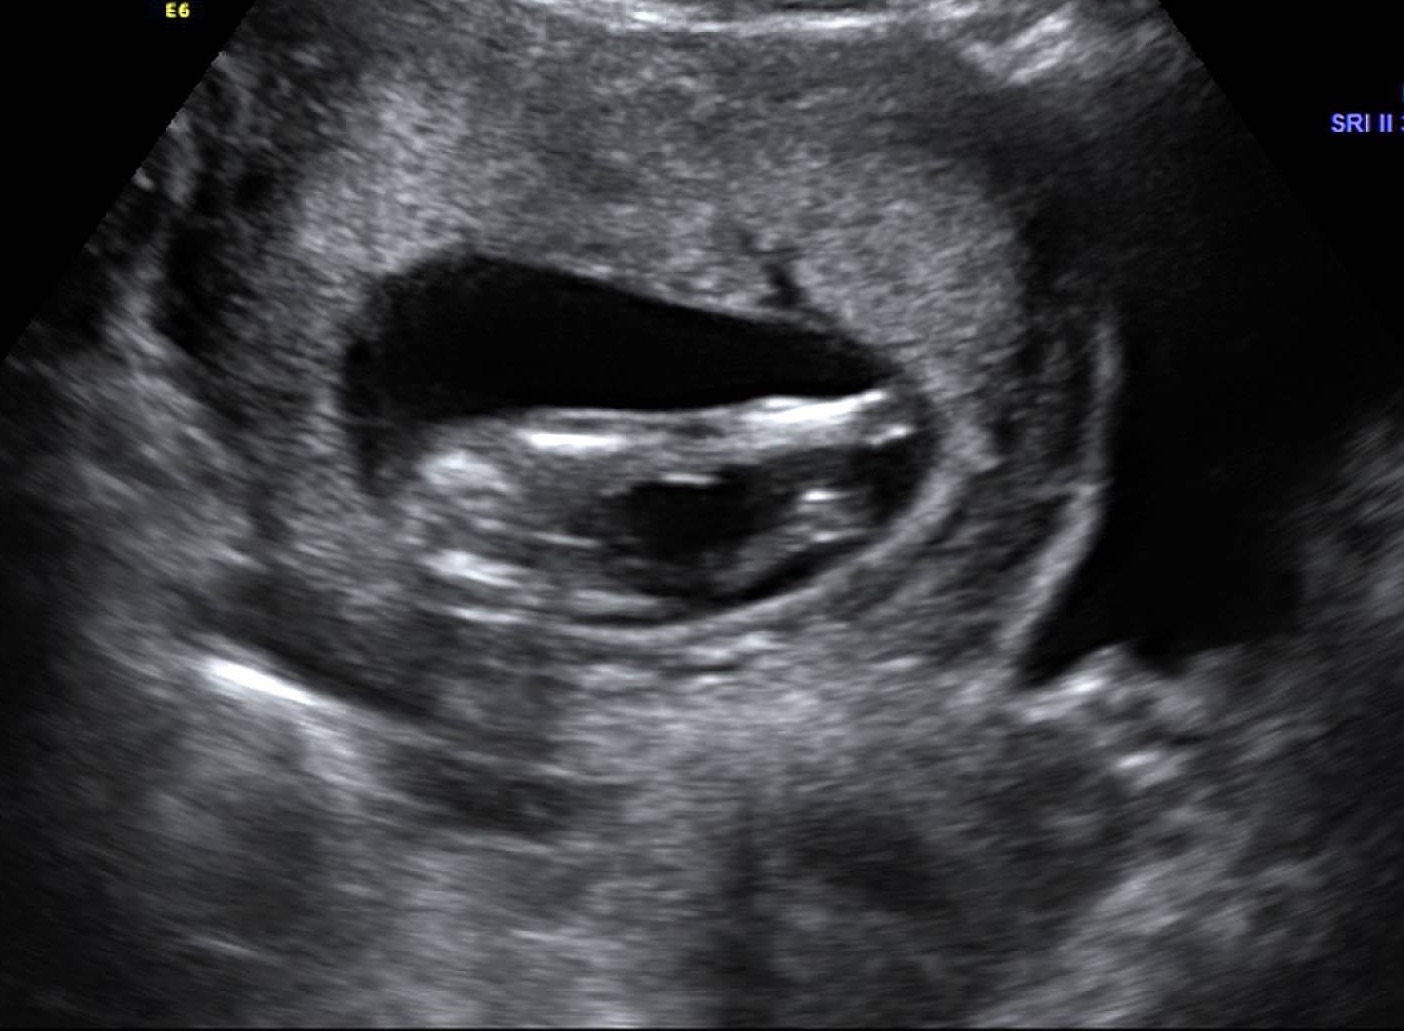

Attachment 24542Attachment 24543Scan was done at 14 weeks 1 day. Any guesses would be appreciated. Thanks!

In the first image, just under the leg you see the nub :) it is angled up and looks to have a bulb shape at the end which would be a boy nub. Girl nubs tend to be long and flat with a thin fork on the end.

I think girl because you're already 14 weeks and the nub is quite parallel to the spine, it won't be rising any more. But it does look a bit like a boy nub too, so don't buy pink from my prediction :) Also I see no sign of a penis on the potty shot, although there is a lot of "noise" around the potty area, so that could theoretically be a penis. I hope you hear girl. When is your next scan?

I'm also thinking girl. The spine is curved up at the end so the nub is pretty parallel and I see a bit of a fork. Good luck!